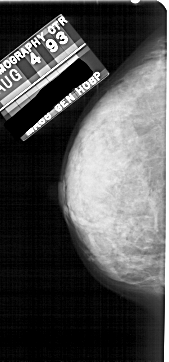

A_1807_1.RIGHT_MLO

RIGHT_MLO LINES 5491 PIXELS_PER_LINE 2461 BITS_PER_PIXEL 12 RESOLUTION 43.5 OVERLAY